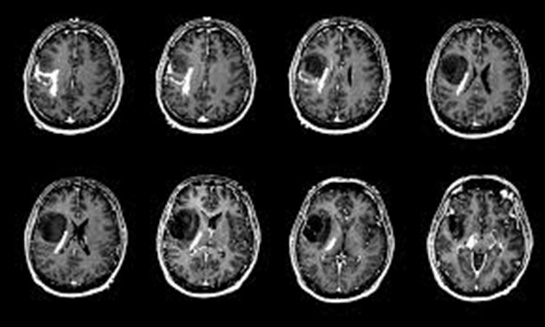

Beyin Tümörü Belirtileri ve TedavisiBeyin tümörü, beyinde veya beyincikte oluşan anormal hücre büyümeleri olarak tanımlanır. Bu tümörler iyi huylu (benign) veya kötü huylu (malign) olabilir. Beyin tümörleri, beynin işlevlerini etkileyerek çeşitli belirtilere yol açabilir. Bu makalede, beyin tümörlerinin belirtileri, tanı yöntemleri ve tedavi seçenekleri hakkında detaylı bilgi verilecektir. Beyin Tümörleri Nedir? Beyin tümörleri, beyin dokusunda oluşan anormal hücre gruplarıdır. Bu tümörler, beyin hücrelerinden (primer tümörler) veya vücudun diğer bölgelerinde oluşarak beyne yayılan hücrelerden (sekonder tümörler) kaynaklanabilir. Beyin tümörleri, büyüklüğü, yeri ve hücresel yapısına göre farklılık gösterir. Beyin Tümörlerinin Belirtileri Beyin tümörlerinin belirtileri, tümörün boyutuna, yerine ve tipine bağlı olarak değişkenlik gösterebilir. En yaygın belirtiler şunlardır:

Beyin Tümörlerinin Tanısı Beyin tümörlerinin tanısı genellikle aşağıdaki yöntemlerle konur: